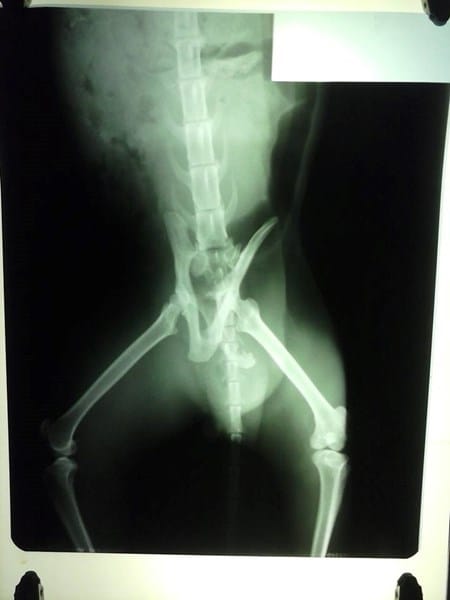

Gato fracturado con tutor externo

Se trata de un gato semi-salvaje que fue atropellado hace 10 días y sufrió fractura de cadera. Se le realizó cirugía y colocó un tutor externo. Sé que el reposo es fundamental (por lo cual lo tengo en una jaula/canil de internación de las que usan en veterinarias), pero mi pregunta es ¿qué tan necesario es el tutor? Él se maneja solo, es decir, va hasta la caja de piedras sanitarias a hacer sus necesidades y hasta el comedero y bebedero. Además, se higieniza y hasta ha saltado para intentar salir. Se nota de todos modos que el tutor le molesta mucho, porque además, los alambres de la parte trasera no son fijos, entran y salen del "agujerito" por donde está incertado. ¿Podría ser posible su recuperación sin el tutor externo?